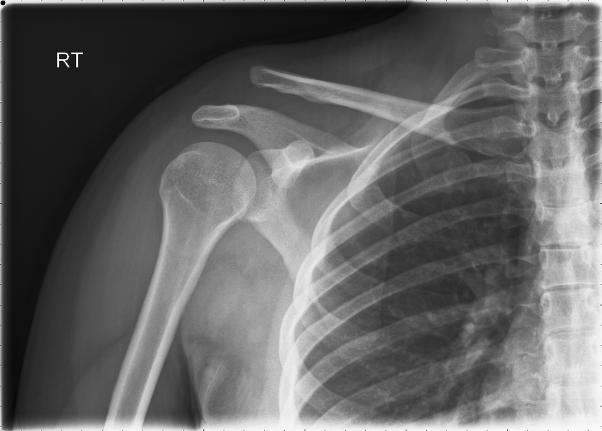

Sports-related injuries Of The shoulder: Instability

Sports-related injuries of the shoulder: instability Joshua M. Farber, MD*, Kenneth A. Buckwalter, MD Department of Radiology, Indiana University School of Medicine, 550 North University Boulevard, ... Access Content

Etiology. 85% of shoulder pain is intrinsic to the shoulder; the remainder is referred usually from the neck. Acute symptoms following trauma is typically due to dislocation, fracture, or rotator cuff tear ... Read Full Source

Chapter 5 Shoulder Injuries - Springer

5 Shoulder Injuries 105 The glenohumeral ligaments represent thickened bands within the joint capsule and attach to both the margin of the ... Fetch Document

SHOULDER INJURIES IN THE ATHLETE

SHOULDER INJURIES IN THE ATHLETE Michael J. Hulstyn, MD, and scapulothoracic. When evaluating the athlete for shoulder complaints, the physician must consider each articu- lation as a source of disorder. Also, pain from other sites, including ... Get Doc

Acute Shoulder Pain - American College Of Radiology

ACR Appropriateness Criteria® 6 Acute Shoulder Pain important role in the evaluation of the postoperative shoulder and in rotator-cuff integrity after shoulder ... Read More